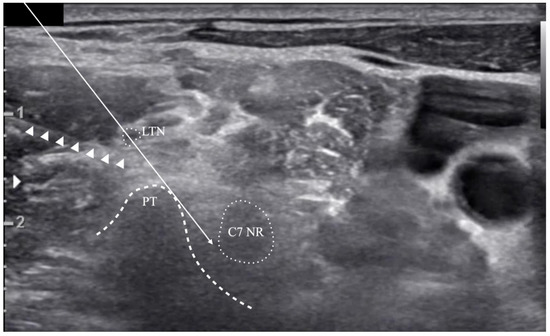

2.2. Simulated Risk Analysis of Long Thoracic Nerve Injury

indicates that it was outside the risk area in the simulated risk analysis. The LTN’s mean location and locational area estimated by the mean ± standard deviation (SD) are presented. The painted area indicates that the needle’s trajectory is expected to be associated with a high risk of LTN injury.